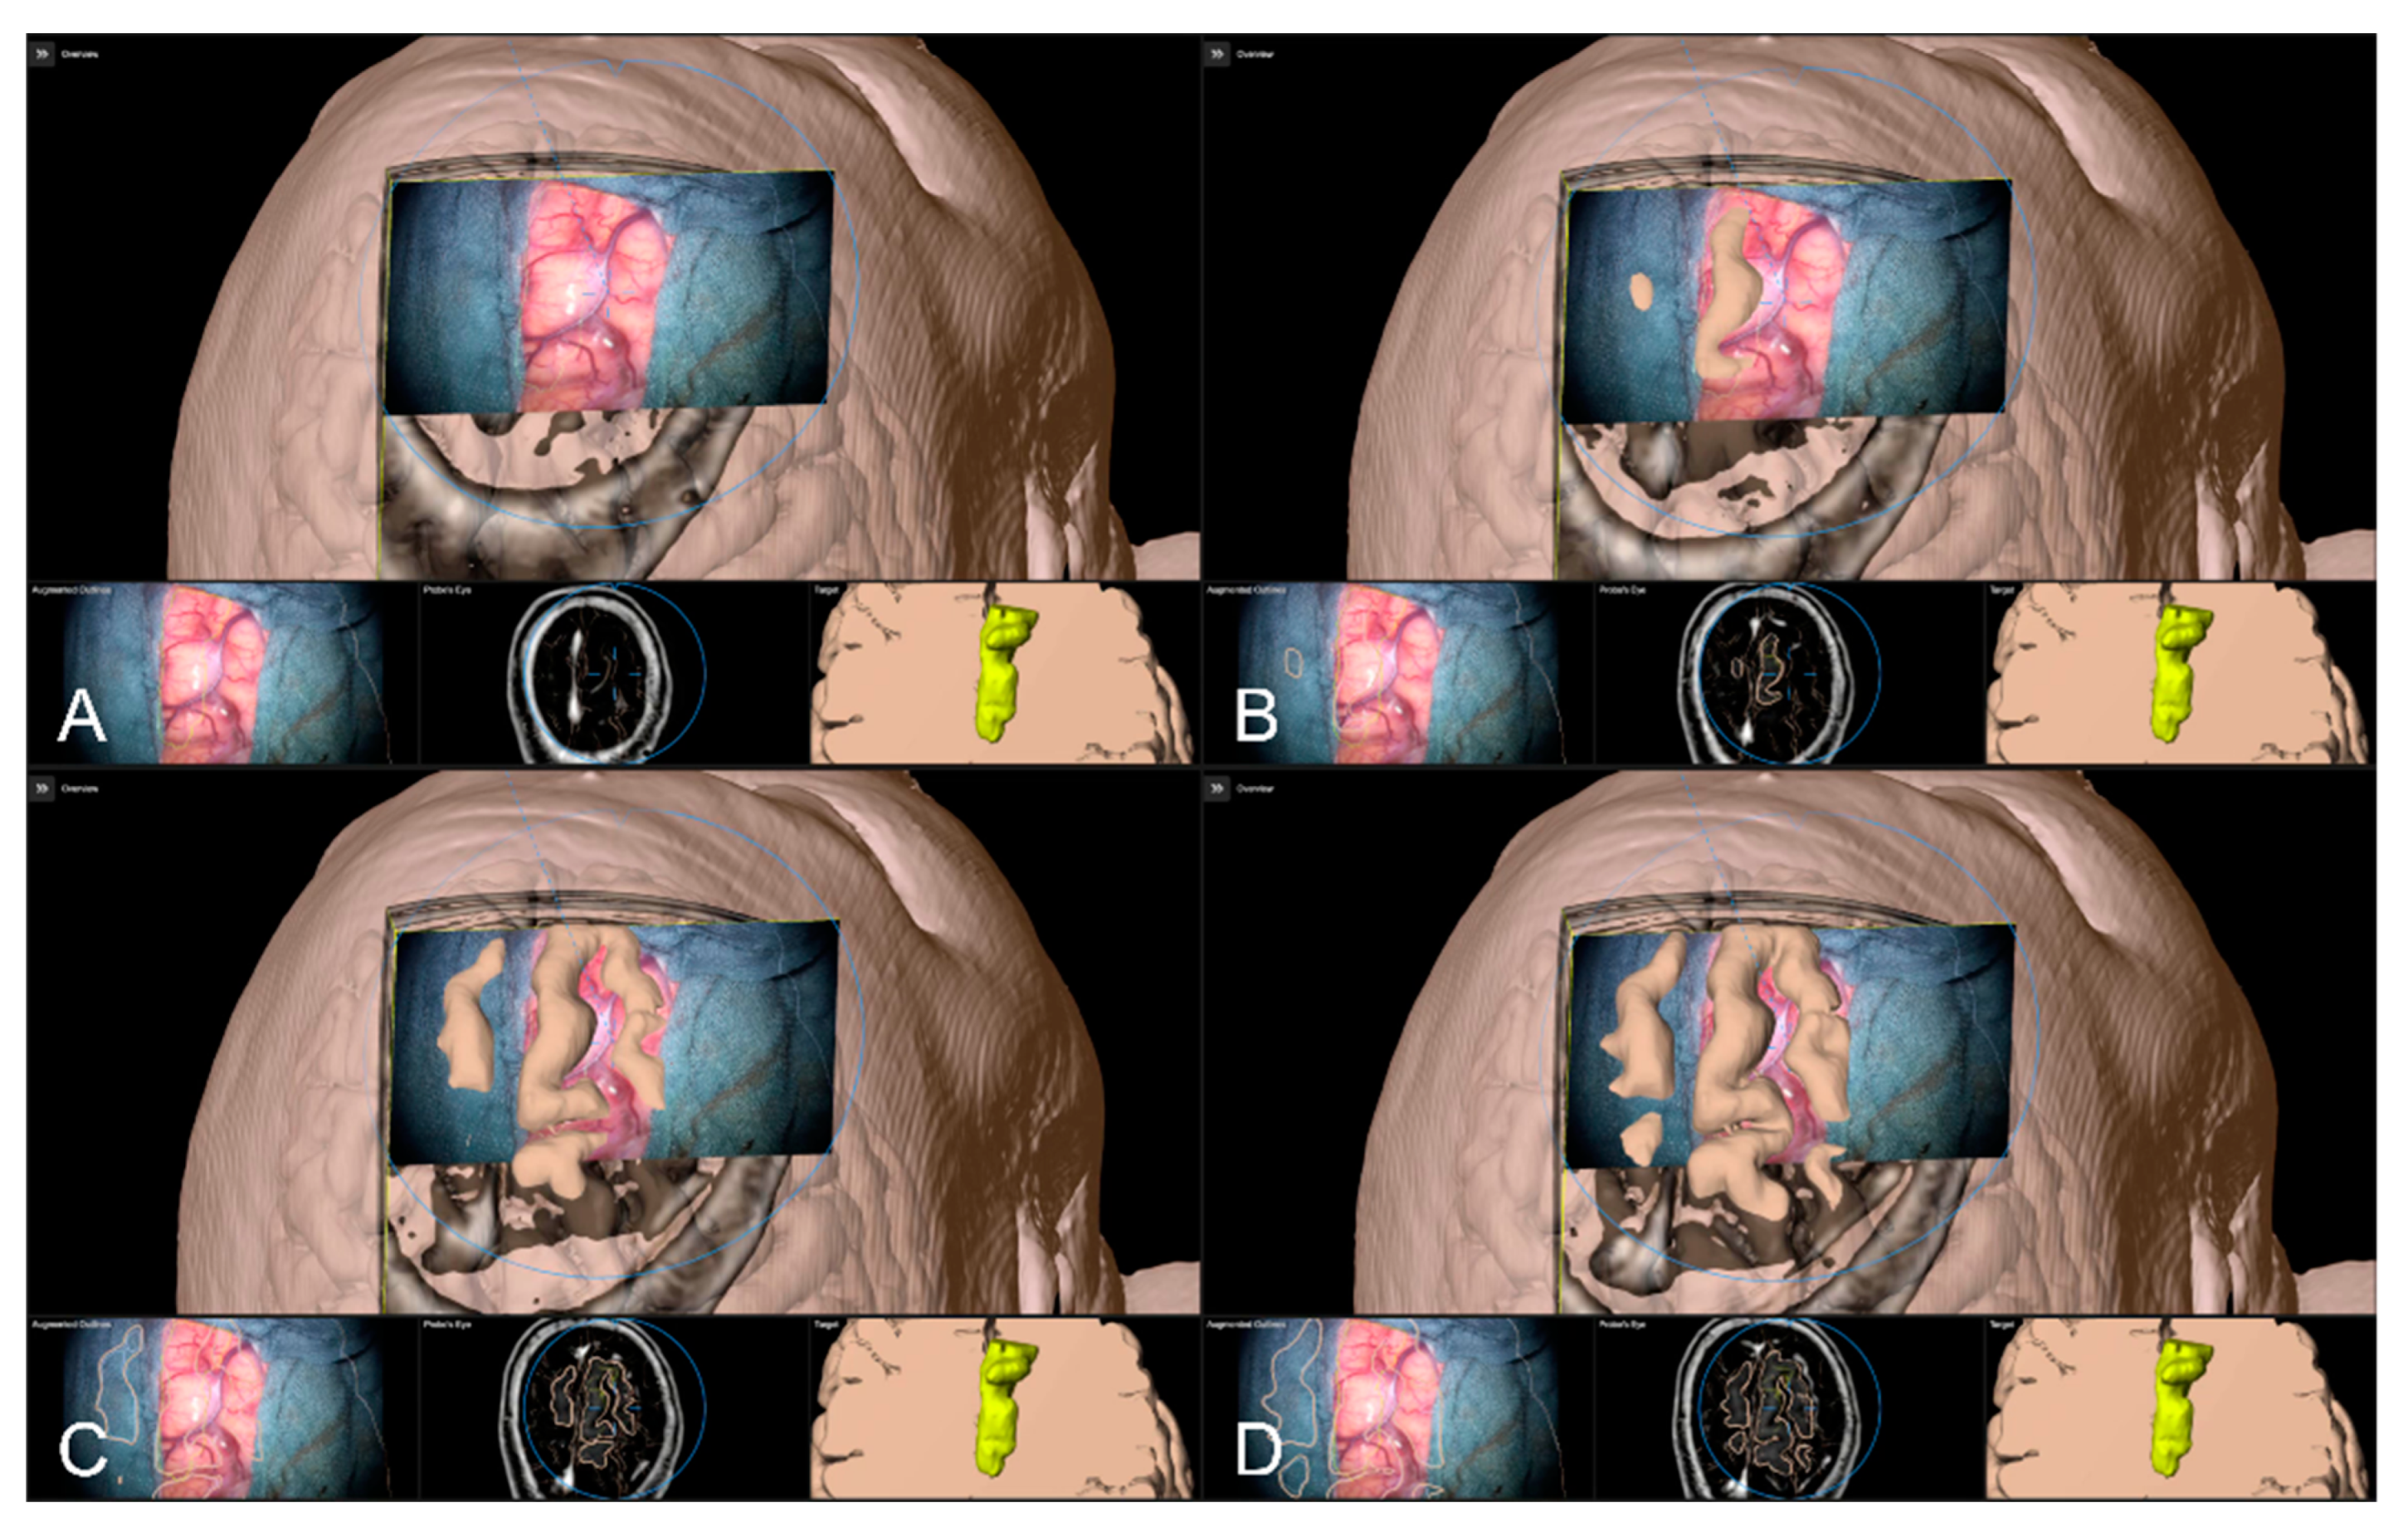

After calibration of the surgical microscope, AR-support including all pre-segmented objects is available. Outlined objects, such as the tumor or vascular or functional risk structures, can then be visualized using the AR display by superimposing the 3D objects in the operating microscope by the integrated HUDs. In parallel, multimodal fused image sets are visualized in the Cranial Navigation Element (Brainlab, Munich, Germany) on a monitor close to the surgical field. In addition, within the Microscope Navigation Element (Brainlab, Munich, Germany) objects can be displayed, e.g., superimposed on the microscope video or within a probe’s eye view of the registered image data. Alternatively, the microscope video can be superimposed on a 3D visualization of the patient data including all objects and relevant pre-segmented structures intuitively relating the microscope video frame and 3D anatomy (see Figure 3).

Figure 3. After calibration of the microscope, besides HUD-based visualization within the microscope, the Microscope Navigation Element (A) and Cranial Navigation element (B) are displayed on monitors close to the surgical field. The microscope application allows for a visualization of outlined objects (yellow: tumor, blue: precentral gyrus, corticospinal tract) superimposed on the microscope video (A, top), or probe’s eye view, target view or outlined 3D anatomy in relation to the microscope video frame (A, bottom, left to right). In parallel, in the navigation application multimodal fused image sets with outlined structures are visualized in, e.g., axial, coronal, and sagittal view (B).

Sensors 22 09591 g003

Figure 9. Superimposing the microscope video on the 3D visualization of patient MRI data including the pre-segmented objects (cerebrum and tumor) intuitively relating video frame and 3D anatomy (upper part in AD), in parallel view of AR-supported microscope view, probe’s eye view and target view (bottom part in AD from left to right). Moving the focus plane (superimposed microscope video) along the optical axis of the microscope (AD), the registration quality can be evaluated showing a sufficient match in this case.

Sensors 22 09591 g009

In addition to the 2D object representation available within the navigation update feature, in the case of the cortex being not as straightforward as in the case of bony or vascular structures, the microscope navigation provides different views to visualize the preoperative image data and the microscope video data during surgery. The Overview View enables the microscope video to be superimposed on a 3D visualization of the patient data including the pre-segmented objects and structures of interest and thereby related intuitively the video frame and the 3D anatomy. By moving the focus plane (superimposed microscope video) along the optical axis of the microscope, the match or mismatch of the cortical representation can be easily detected. In case of a mismatch, another navigation update needs to be performed.

Alternative to bony and/or vascular landmarks, in 40 cases (13.65%) a cortex representation gained by automatic segmentation of cranial structures was used to evaluate and verify navigational accuracy. As the in-plane object representation is not straightforward, the Overview View was used firsthand in all cases to evaluate navigation accuracy allowing for superimposing the microscope video on the 3D visualization of the segmented data, see Figure 9. If a mismatch was seen, switching to the navigation update feature allowed for an in-plane transformation of the date to overcome the seen misalignment in the focus plane. This was the case in two patients (5.00%), whereas in the remaining 38 cases (95.00%), there was no need for further alignments was seen. In both cases, a linear transformation by on average 5.31 ± 1.57 mm and 1.75° ± 2.47° led to sufficient accuracy.